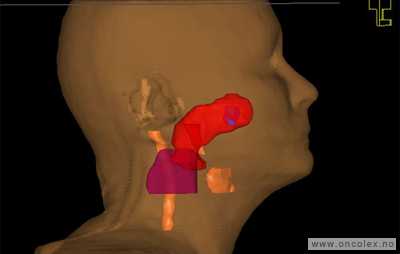

Målvolum

Skisse over hvordan strålefeltet planlegges:

• GTV (Gross Tumor Volume): Identifisert tumor.

• CTV (Clinical Target Volume) GTV + omkringliggende vev hvor det kan væremikroskopisk spredning.

• ITV (Internal Target Volume): CTV + en indre margin som tar hensyn tilindre bevegelser og endringer av CTV.

• PTV (Planning Target Volume): Innstillingsmargin som inneholder ITV og samtidig tar hensyn til antatte pasientbevegelser, samt variasjoner i pasientopplegging og feltinnstillinger.

• Feltgrense. Tegnes som oftest på kroppen.

ICRU (International Commission on Radiation Units and Measurements)